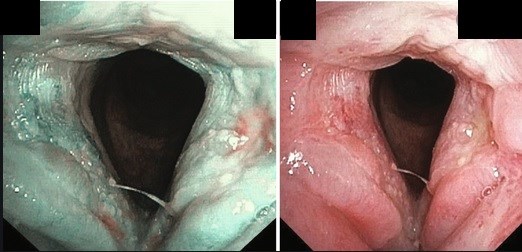

Классическая эндоскопическая картина при гортанно-глоточном забросе

- эритема черпалонадгортанной области;

- отек задней комиссуры и межчерпаловидного пространства;

- атрофия или гиперкератоз голосовых складок;

- гиперемия подскладочного пространства и первых колец трахеи;

- скопление слизи в грушевидных карманах.

Изменения гортани при узкоспектральной эндоскопии (NBI-endoscopy)